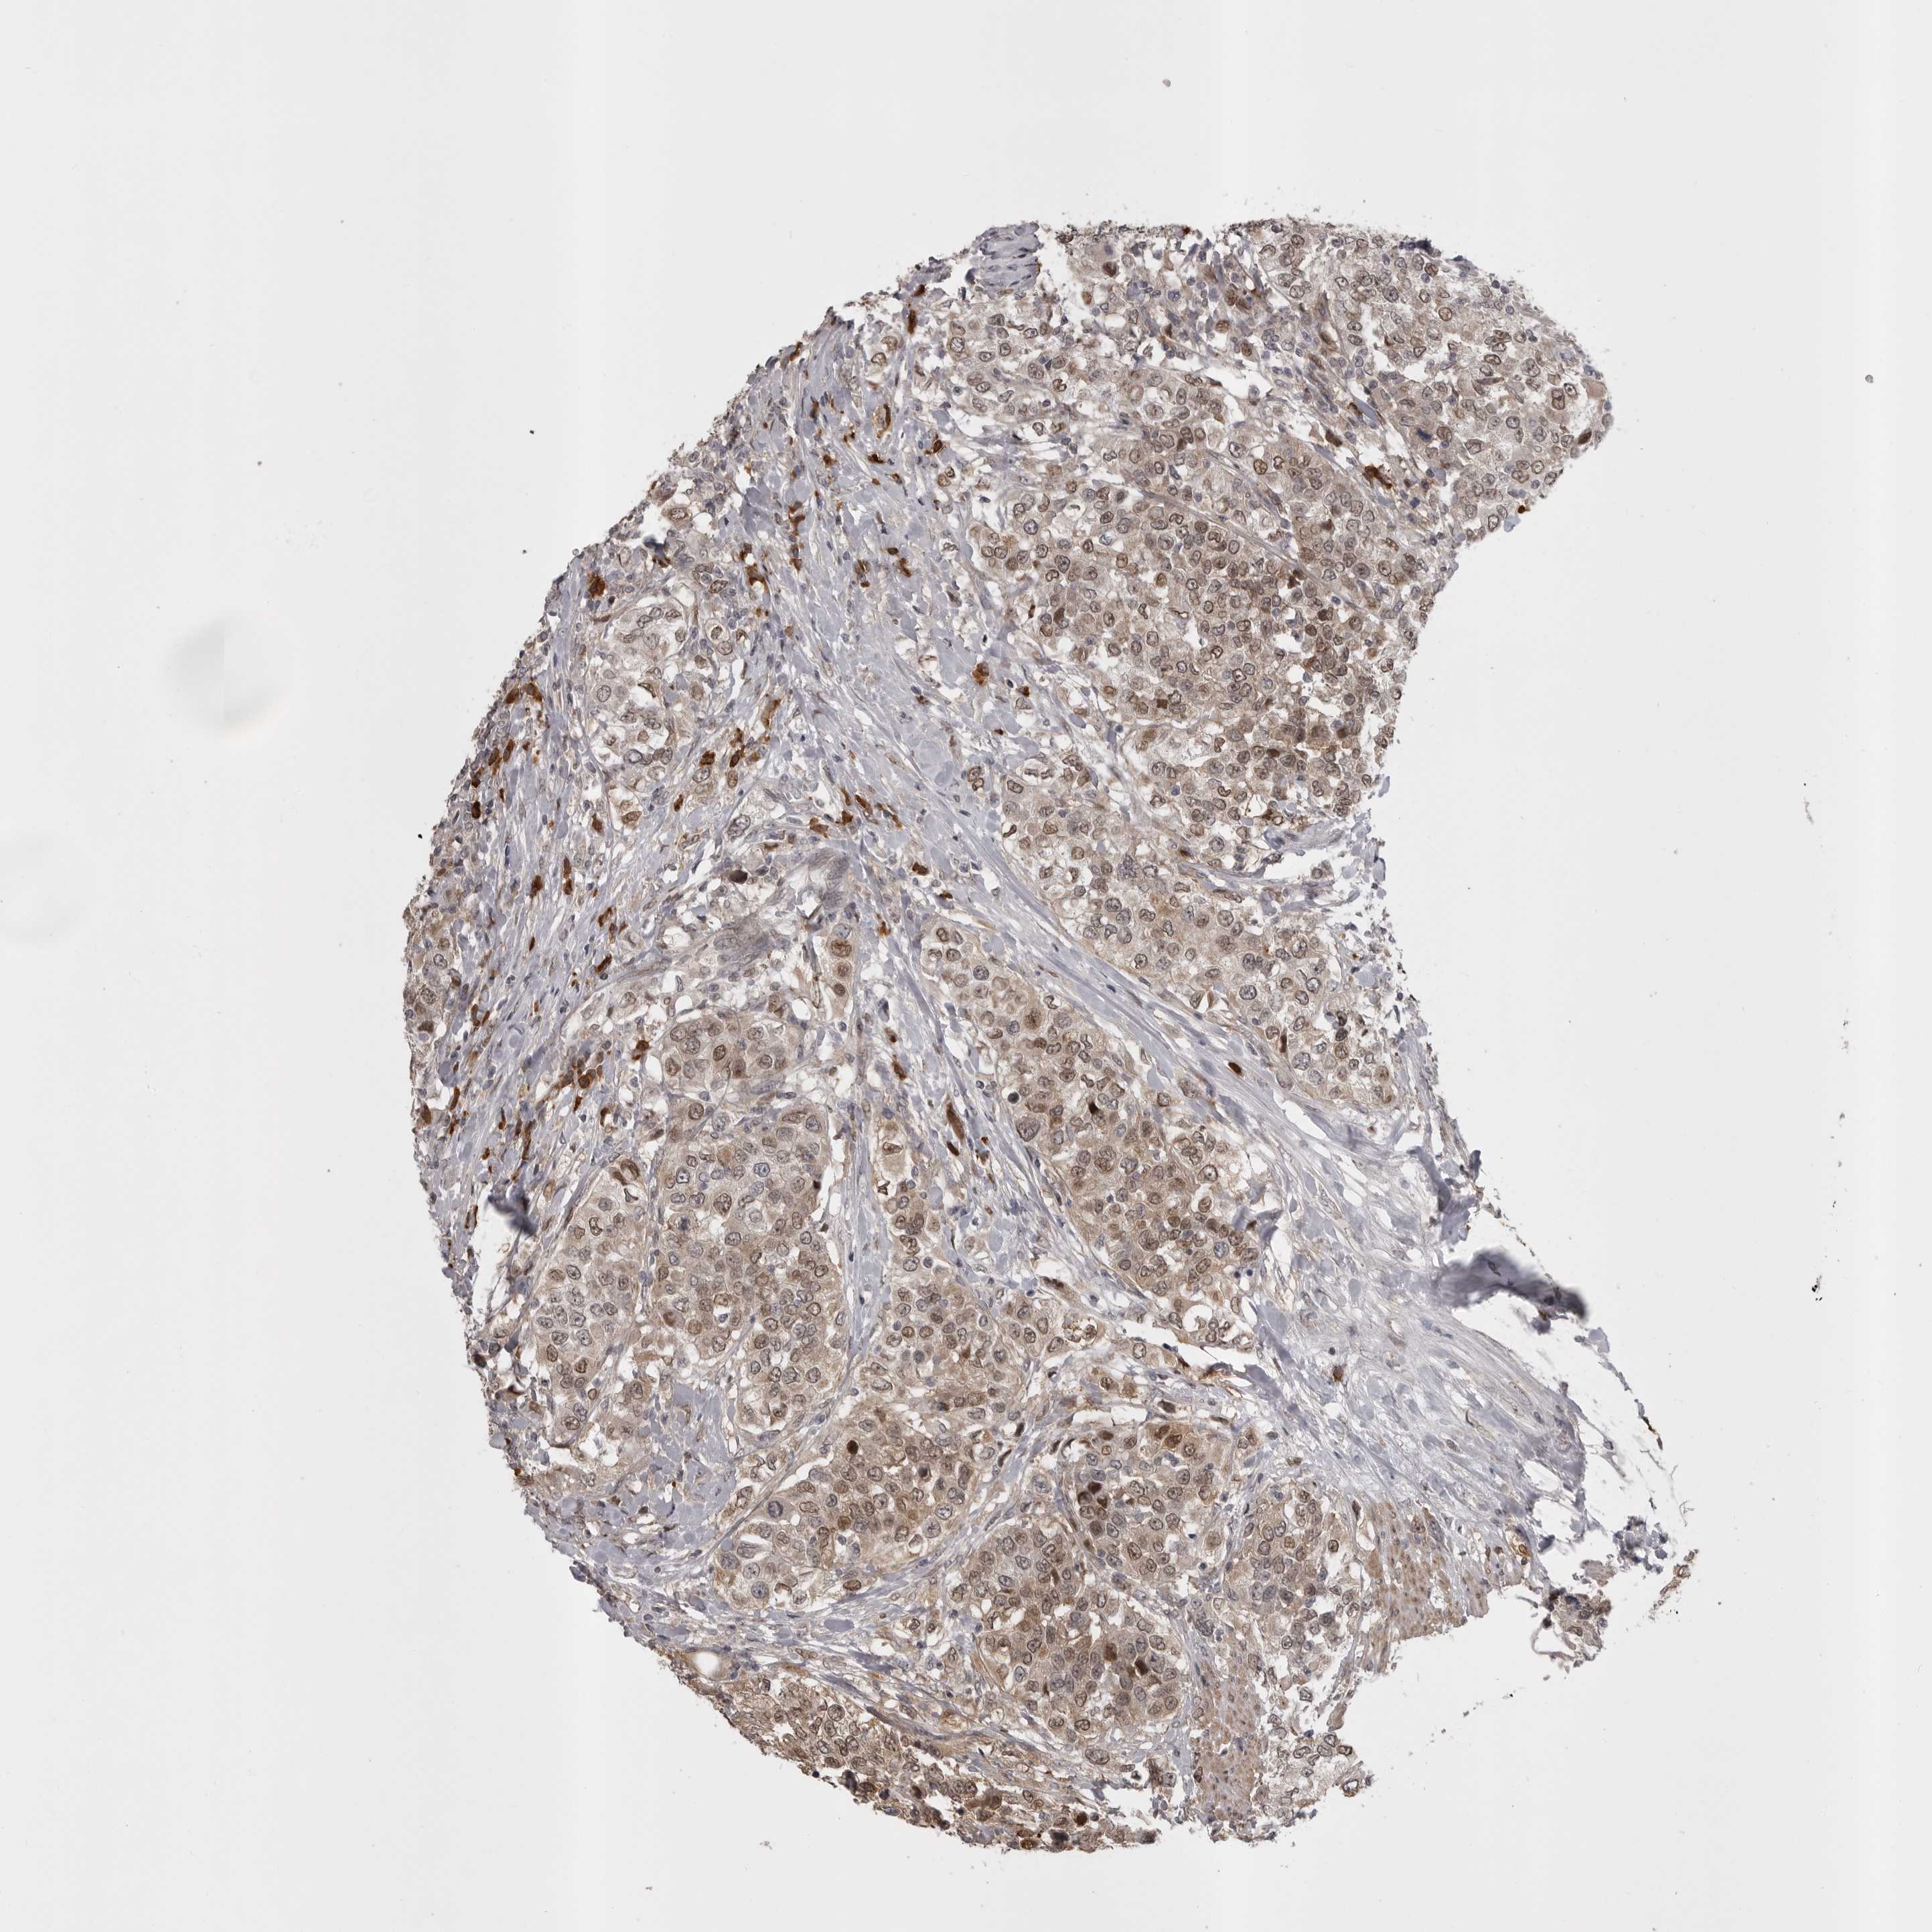

UROTHELIAL CANCER - Protein expressioni

A mouse-over function shows sample information and annotation data. Click on an image to view it in a full screen mode. Samples can be filtered based on level of antibody staining by selecting one or several of the following categories: high, medium, low and not detected. The assay and annotation is described here.

Note that samples used for immunohistochemistry by the Human Protein Atlas do not correspond to samples in the TCGA dataset.

Antibody stainingi

Antibody staining in the annotated cell types in the current human tissue is reported as not detected, low, medium, or high, based on conventional immunohistochemistry profiling in selected tissues. This score is based on the combination of the staining intensity and fraction of stained cells.

Each image is clickable and will lead to virtual microscopy that enables deeper exploration of all samples and also displays staining intensity scores, fraction scores and subcellular localization as well as patient and tissue information for each sample.

Antibody HPA024730

Antibody HPA024731

Antibody HPA024817

Staining

High

Medium

Low

Not detected

Intensity

Strong

Moderate

Weak

Negative

Quantity

>75%

75%-25%

<25%

None

Location

Nuclear

Cytoplasmic/membranous

Cytoplasmic/membranous,nuclear

Urothelial carcinoma, Low grade

Urothelial carcinoma, High grade